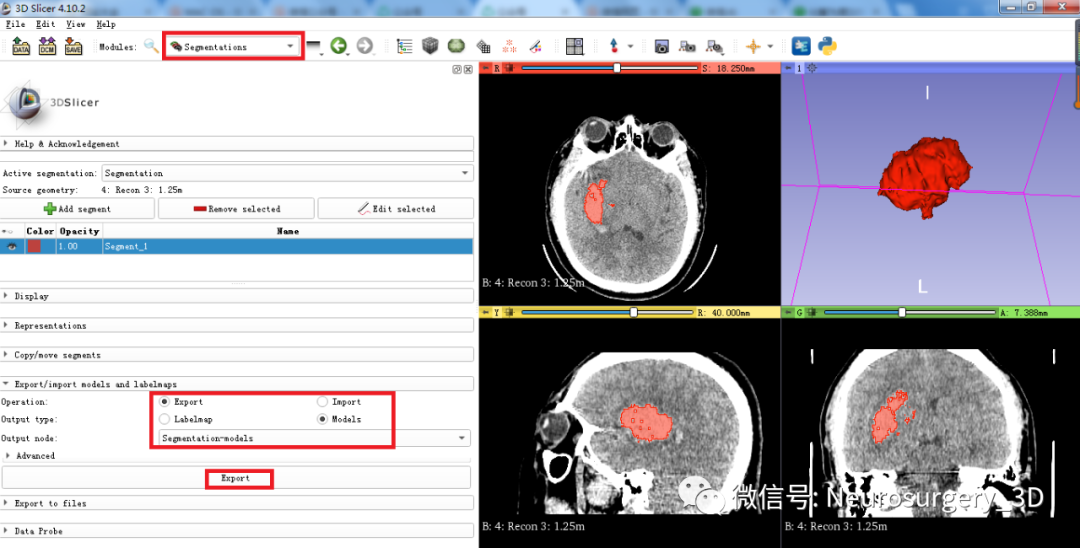

5、利用segmentations分割工具生成血肿Models模型

在Models血肿模型中可自动计算血肿体积19.74ml